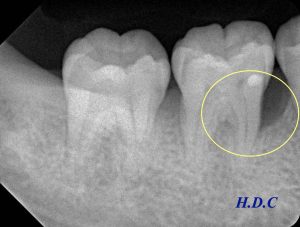

左のレントゲンが初診時、右のレントゲンがエムドゲイン治療後6年経過時です。

初診EMD2EMD6Y

エムドゲインによって、歯の周囲の骨が再生し、長期間安定しているのがわかります(黄色い枠の中)。